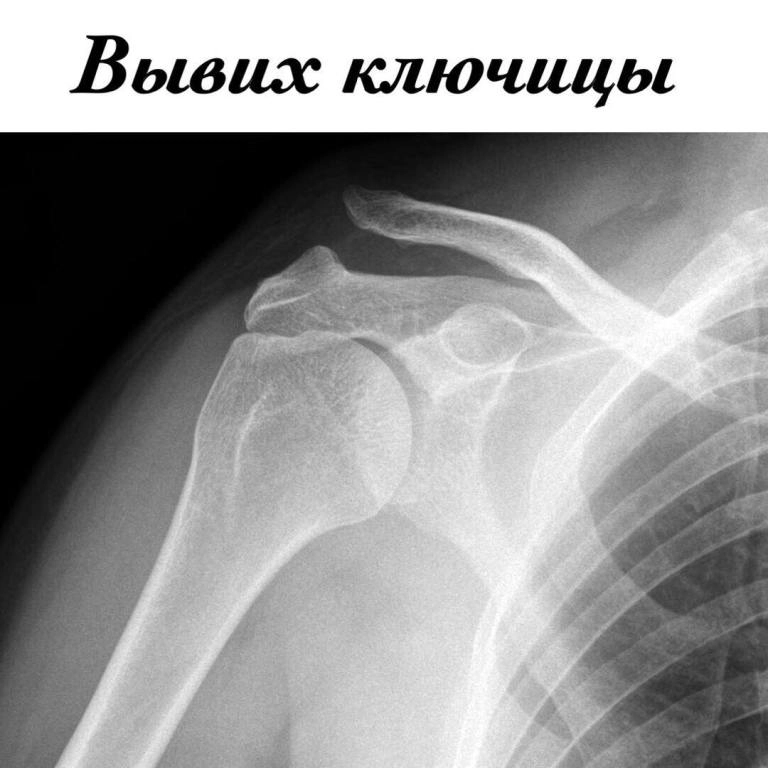

• Артроскопия проводится с использованием щадящих технологий, позволяющих лечить повреждения плечевого, коленного, локтевого

и голеностопного сустава с минимальной травматизацией.